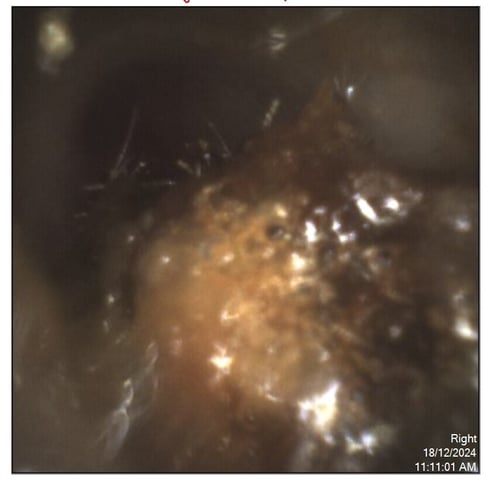

In this image you can see the ear canal is blocked with a large ball of wax The patient reported feeling blocked and sound was muffled The wax had built up inside the ear canal and was blocking access to the ear drum

Before and After: The Difference Wax Removal Can Make

Many patients are amazed by the transformation after wax removal. Images of ears before and after the procedure clearly show the difference: from blocked ear canals to clean, open pathways. Beyond the visible change, patients often report significant improvements in hearing clarity, reduced discomfort, and relief from symptoms such as itching, ringing, or fullness in the ears.